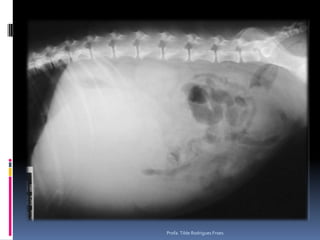

Animal: NEGUER, canino, macho, 11 anosHx: Ascite, sinais de creptação e sopro na ausculta pulmonar - asciteProfa. Tilde Rodrigues Froes

Profa. Tilde Rodrigues Froes

Animal: NEGUER, canino,macho, 11 anosHx: Ascite, sinais de creptação e sopro na ausculta pulmonar - asciteProfa. Tilde Rodrigues Froes

• 24.